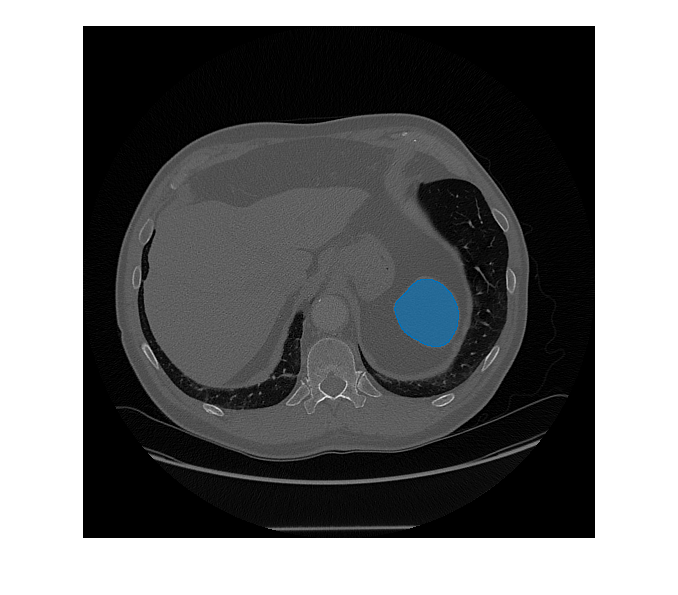

Segment objects in medical image using Medical Segment Anything Model (MedSAM) image embeddings

[

segments objects from an image of size mask,score] = segmentObjectsFromEmbeddings(medsam,embeddings,imageSize,BoundingBox=boxPrompt)imageSize using the Medical

Segment Anything Model (MedSAM) image embeddings embeddings and the

bounding box coordinates boxPrompt as a visual prompt, and returns the

predicted object mask mask and the corresponding prediction score

score.